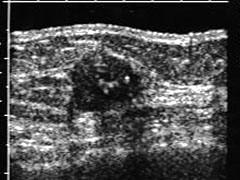

Achados:

- Nódulos sólidos com forma irregular e contornos irregulares.